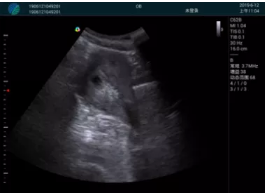

清晰顯示孕囊,通過軟件包計(jì)算孕齡7w+6d

M20實(shí)時(shí)引導(dǎo),術(shù)中清晰顯示孕囊被破壞和抽吸針的過程,清晰顯示吸引針

抽吸結(jié)束后縱切子宮,孕囊已被完全抽吸,未見明顯殘留

橫切子宮,發(fā)現(xiàn)右側(cè)宮腔靠近宮角處有少許脫模樣殘留

M20引導(dǎo)下,抽吸針找到右側(cè)宮角處再次清掃

二次抽吸后再次進(jìn)行超聲檢查,宮腔未見殘留,宮腔線清晰顯示

超聲引導(dǎo)下可視化人流是技術(shù)安全性的保障,一般對人流術(shù)設(shè)備預(yù)算不高,M20具備婦產(chǎn)科軟件包,且穿透力圖像質(zhì)量好,既滿足人流引導(dǎo)需要,也可用于床旁超聲的需求。